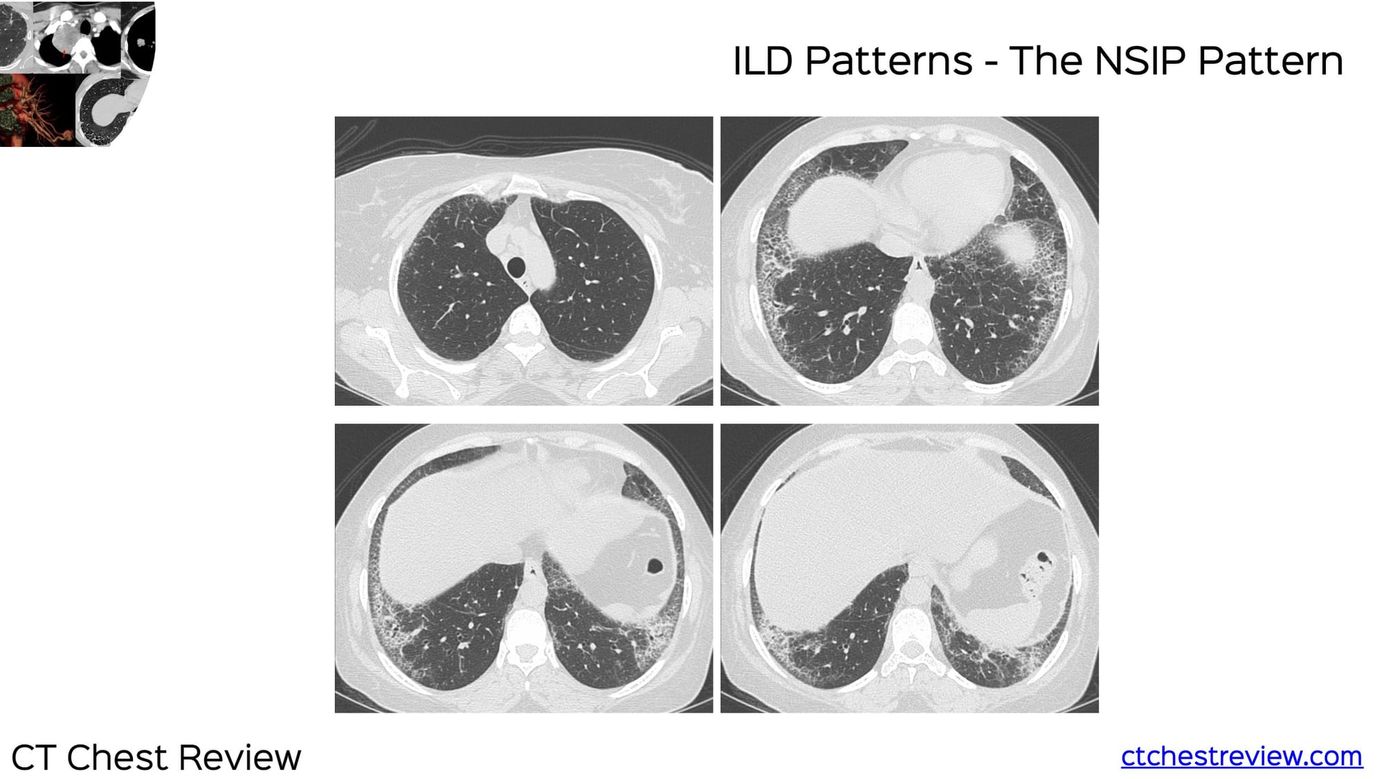

The mimics are

Expiratory, poor breath-hold

Edema

Gravity dependent densities

Friction fibrosis

Aspiration changes

Inflammatory bronchiolitis

The video explains which mimics the patient has that simulate ILD.